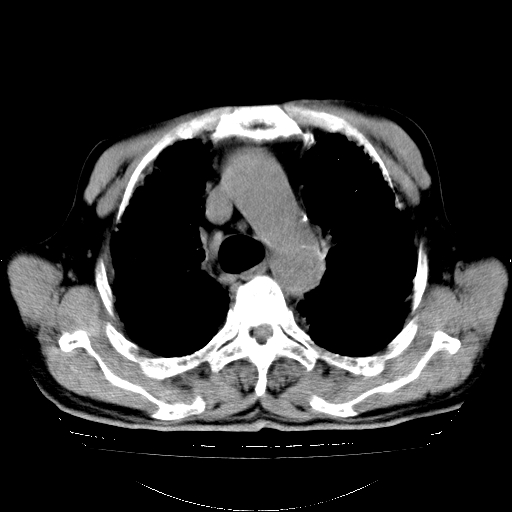

标题: CT25149:男,69岁,反复咳嗽、咳痰五年余,呼吸困难三天。 [打印本页]

男,69岁,反复咳嗽、咳痰五年余,呼吸困难三天。

慢支伴感染、肺气肿、肺心病

慢支伴感染、肺气肿、肺心病!支持!另:间质纤维化!

两肺间质性炎症并感染,左上叶肉芽肿

考虑慢性间质性肺炎并肺间质纤维化。

慢支伴感染、肺气肿、肺心病。双肺间质性改变(间质纤维化)。